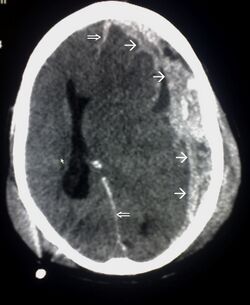

CT scan showing spread of the subdural hematoma (single arrows), midline shift (double arrows)

Systems also exist to classify TBI by its pathological features.[20] Lesions can be extra-axial, (occurring within the skull but outside of the brain) or intra-axial (occurring within the brain tissue).[24] Damage from TBI can be focal or diffuse, confined to specific areas or distributed in a more general manner, respectively.[25] However, it is common for both types of injury to exist in a given case.[25]